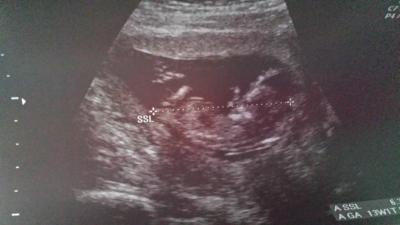

Also nackenmessung alles ok mit 1,2 und das baby hat 6,39 cm liegt schön in seiner position und weis wann man mittagsschlaf hält ...ne halbe stunde hat sie gebraucht um gut nessen zu können...geschlecht darf sie noch nicht schätzen da wegen abtreibunggefahr gesetzlich verboten ist...war heut ganz schön viel aber schön zu sehen das es dem würmchen gut geht... wie war es bei euch heut? Ach ja nächster termin 07.10. für die akten grins

Bild zu bin zurück vom fa - Forum für April - Mamis